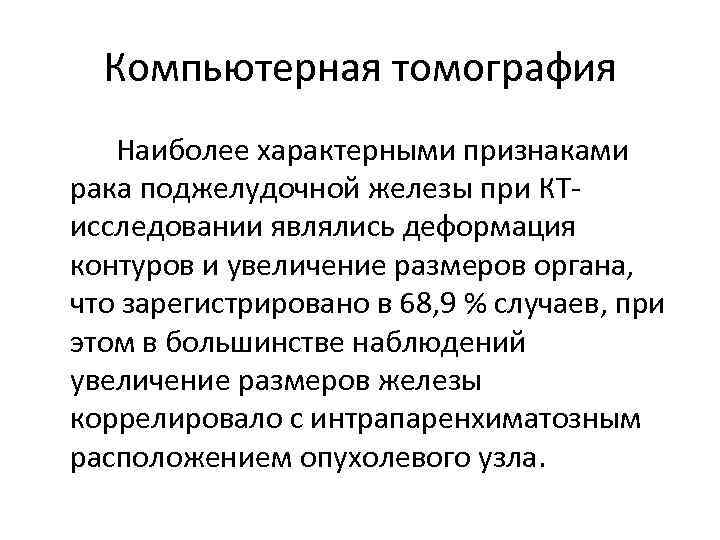

Компьютерная томография Наиболее характерными признаками рака поджелудочной железы при КТисследовании являлись деформация контуров и увеличение размеров органа, что зарегистрировано в 68, 9 % случаев, при этом в большинстве наблюдений увеличение размеров железы коррелировало с интрапаренхиматозным расположением опухолевого узла.